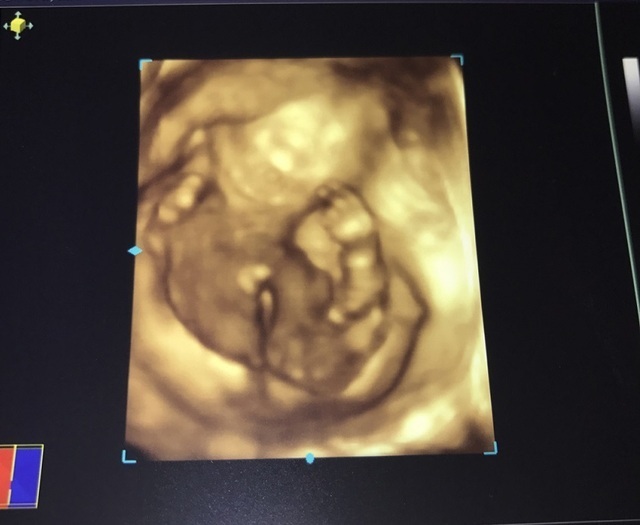

19週3日(19w3d・女の子)|新妻いまい さん(27歳)

エコー写真撮影時のエピソード:

初めての4Dのエコーでしたが、あまりわかりませんでした。 かろうじて女の子ということがわかりました。

どんなエコー写真を持って帰って見せて説明しても、全くわかってくれない旦那に毎回イライラしてた覚えがあります。